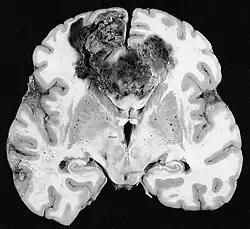

Melanoma

Melanoma is an aggressive skin cancer which has been shown to utilize both angiogenesis and vascular mimicry to drive metastasis and also increase treatment resistance.[1] Metastatic melanoma has very poor survival outcomes with a median survival of 6 months.[19] VM has been identified to be present only in metastatic and very aggressive melanomas. Major biomarkers of VM in melanoma include: VEGF-A, HIF-1A, and Nodal.